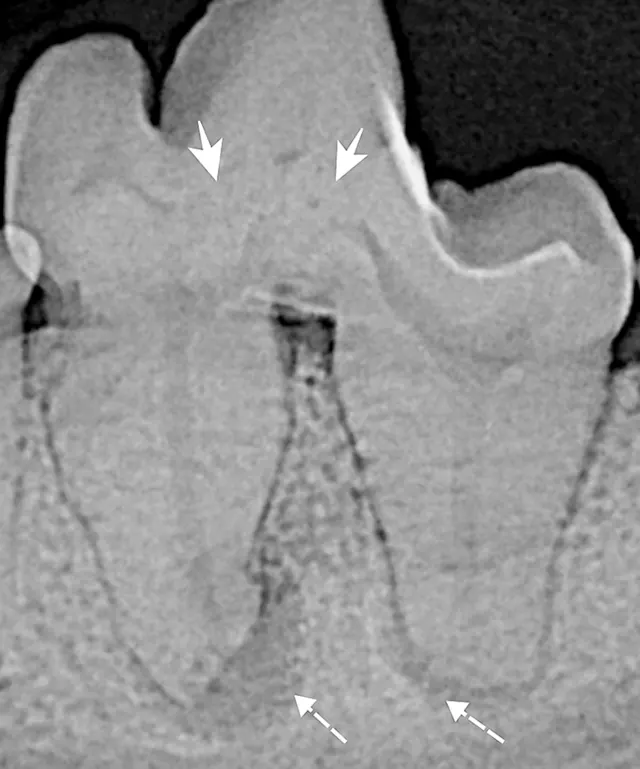

The shape of the crown and/or root can also give insight into any developmental abnormalities of the tooth that can potentially affect vitality (Figures 4 and 5).

Dental radiography can be used to evaluate tooth structure anomalies and root pathology and to assess pulp canal size. Assessment of pulp canal size can be particularly useful for diagnosing nonvital teeth. A common misconception is that after a tooth dies, the canal becomes uniformly wider. In reality, the canal appears wider as compared with other canals because it stopped producing dentin at the time it became nonvital (Figure 7). Vital teeth with intact pulp have odontoblasts that will continue to produce secondary dentin, causing the pulp chamber to continue to narrow.4 Presence of periapical lucencies (Figure 8) and root resorption on dental radiographs are other indicators that a tooth is nonvital.

If the insult to the tooth happened recently, the pulp chamber size will be the same as the contralateral tooth. Repeat radiographs in 6 months may show that the pulp chambers of vital teeth will continue to narrow and the nonvital tooth pulp chamber will appear larger. Of note, it can be difficult to evaluate subtle changes in canal size in mature dogs with narrow canals.